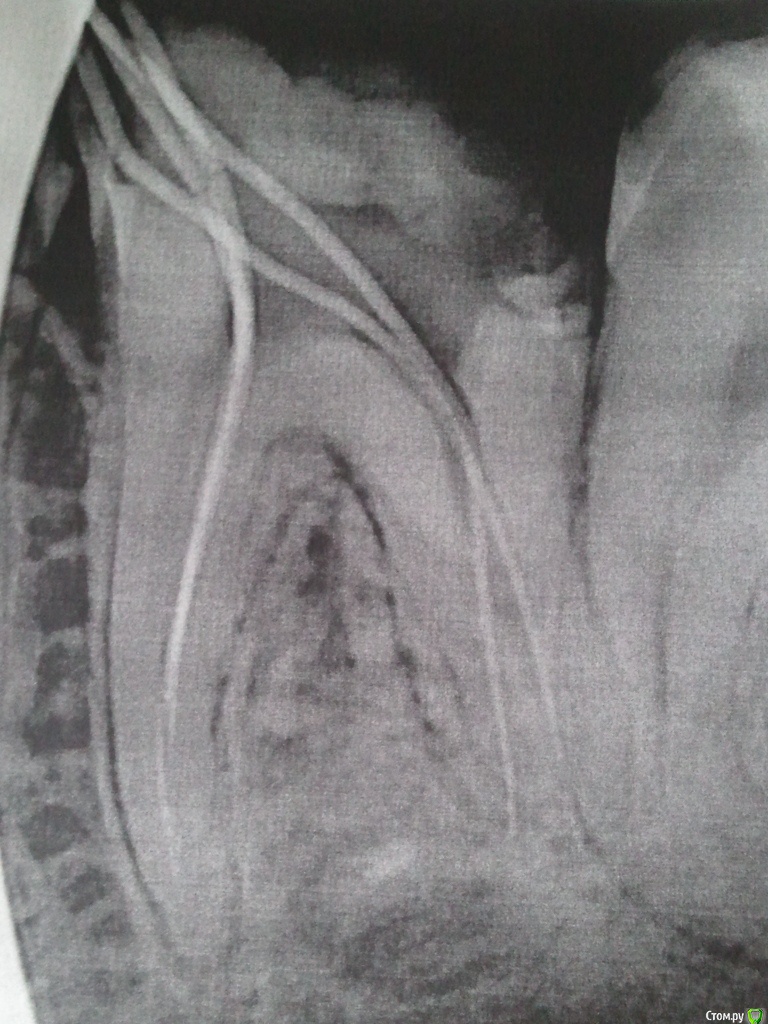

LexIgnatov Опубликовано 1 декабря, 2015 Автор Поделиться Опубликовано 1 декабря, 2015 (изменено) Здравствуйте. Вновь прошу совета.Итак, в "предыдущих сериях"... Шестой зуб слева для меня (Или справа глазами доктора).Исходное состояние перед лечением:Не очень понимаю что где, но для лечения обратился потому что отвалилась пломба на этом зубе.17.11.2015 Убран глубокий кариес, положена какая-то мазь для заживления-успокоения нерва. Через день нерв начал стрелять.20.11.2015 Положили параформальдегидную (насколько я понял) пасту для умерщвления нерва (позже выяснилось что там 4 канала). Боли сменились на лёгкие ноющие с редкими покалываниями.23.11.2015 Сделан снимок ОПТГ.Записали на приём 5.12.2015 к стоматологу-ортодонту, чтобы решить что делать с 7 и 8 зубами. Дело в том, что 7-й зуб наполовину сверху прикрыт десной. А на открытой части виден кариес. Сказали что если ортодонт скажет, что можно сохранить 7 и 8 зубы, то нужно удалить часть десны над 7-ым и попробовать вылечить кариес. Говорят что судя по снимку нервы в нём можно будет не удалять. Пугает, что когда 6-й лечили, тоже говорили, что попытаются сохранить нервы - однако после болей пришлось их удалить. Проблема в том, что у меня рот плохо открывается, и если потребуется депульпирование 7-го, то туда будет очень сложно залезть. Другой вариант как они сказали - удалить 7-ки, а через их полость удалить и 8-ки. Но это меня пугает, всю челюсть перепахают. У матери (50 лет) 8-ки до сих пор не прорезались и не беспокоят.27.11.2015 Удалили 4 нерва в 6-м зубе без анастезии. Два нерва удалялись с болью несмотря на девитализацию, сделали внутрь каналов местную анестезию - пошло лучше. Во время чистки каналов где-то сильно дёргало, чистили пока не перестало дёргать. Поставили гуттаперчи с противовоспалительным раствором и временную пломбу на 11 дней. Сказали что потом будут ещё раз чистить каналы и пломбировать их на постоянку. Зачем второй раз чистить? Не хочу снова подпрыгивать в кресле))Снимок в процессе установки гуттаперчи:PS. Ещё не понятно как восстановить коронковую часть зуба. От него фактически остались две стенки - со стороны щеки и языка, а остальное пломба. Хочется понять как грамотнее поступить, что посоветуете? Спасибо.PS2. Редкие слегка покалывающие боли сейчас (пока лежит противовоспалительное) в моём случае нормально или нет? Иногда ощущение, что от пульса отдаёт, при приседании. А иногда даже от активной мимики. Или это может реагировать плохой соседний пятый зуб? И можно ли есть на таком зубе? Я вот побаиваюсь и ем на другой стороне. Изменено 1 декабря, 2015 пользователем LexIgnatov Ссылка на комментарий